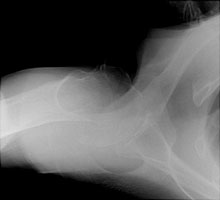

- Click on the image for a larger versionBAxillary view of the left shoulder. The single fracture with minimal displacement is better seen (Neer one-part).